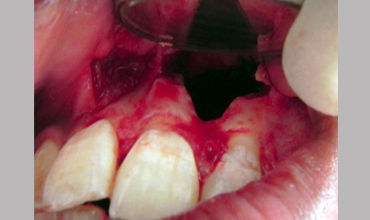

Surgical Management Of Large Periapical Cyst